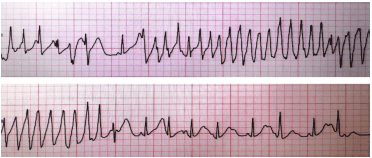

Paciente do sexo masculino de 29 anos, com diagnóstico de Covid-19 na sua forma leve, dá entrada no pronto-socorro com quadro de pré-síncope, mal-estar generalizado e palpitações. Refere estar fazendo uso de um kit Covid prescrito, contendo hidroxicloroquina, azitromicina e ivermectina.

Ao exame, paciente diaforético, hipotenso e com sinais de má-perfusão periférica. Paciente foi monitorizado em desfibrilador e obtido o seguinte traçado elétrico:

Considere as seguintes opções terapêuticas:

I. Sulfato de magnésio

II. Amiodarona

III. Cardioversão elétrica sincronizada

IV. Desfibrilação

Para esse paciente, são factíveis de serem realizadas